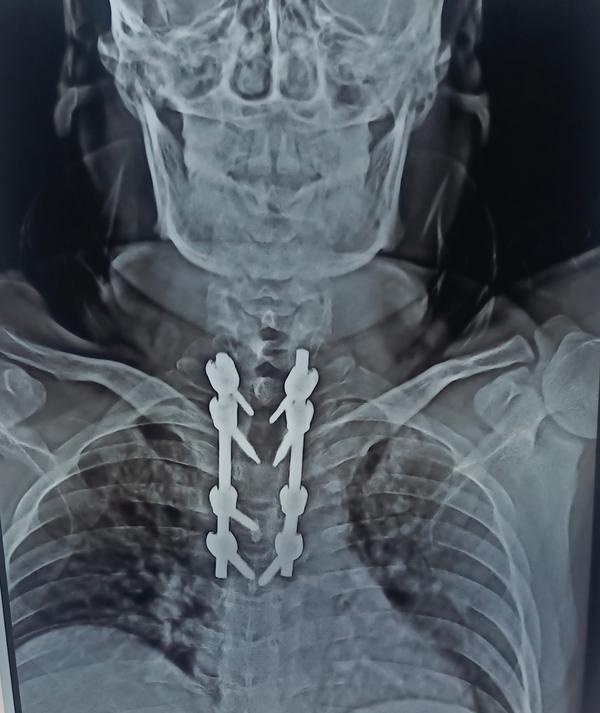

BEST SPINE SURGEON IN PUNE ! BEST SPINE SPECIALIST IN PUNE ! DR. NITISH AGARWAL

ARE YOU LOOKING FOR SPINE FRACTURE TREATMENT IN PUNE

SPINE FIXATION WITH DECOMPRESSION DISCECTOMY IS TH...